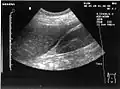

The hepatorenal recess[1] (subhepatic recess, pouch of Morison or Morison's pouch) is the subhepatic space that separates the liver from the right kidney. As a potential space, the recess is not normally filled with fluid. However, fluid can collect here in circumstances where the abdomen fills with fluid, such as hemoperitoneum. This fluid may be seen on ultrasound or computed tomography (CT scan).

Since it is a potential space, the hepatorenal recess is not normally filled with fluid. However, this space becomes significant in conditions in which fluid collects within the abdomen (most commonly ascites and hemoperitoneum). The intraperitoneal fluid, be it blood, ascites, or dialysate, collects in this space and may be visualized, most commonly via ultrasound or computed tomography (CT) scanning. As little as 30 or 40 ml of fluid in the abdominal cavity may be visualized in this space.

Early visualization of fluid in the hepatorenal recess on FAST scan may be an indication for urgent laparotomy.[2]